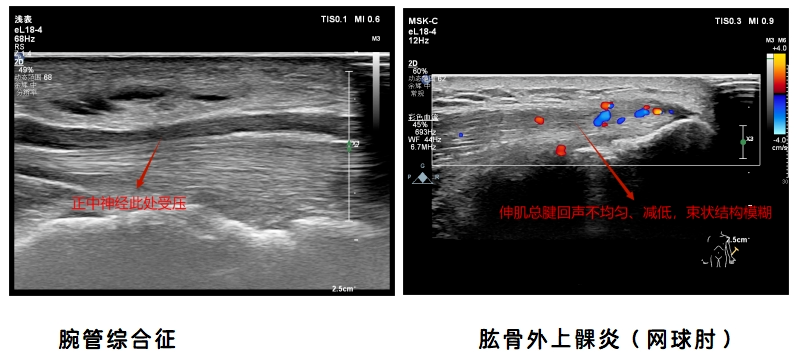

3.腕关节超声检查:腕管综合征、桡骨茎突狭窄性腱鞘炎(妈妈手)、扳机指、类风湿性关节炎、拇长屈肌腱断裂等。

2.肘关节超声检查:肘管综合征、肱骨内上髁炎(高尔夫球肘)、肱骨外上髁炎(网球肘)、尺骨鹰嘴滑囊炎等。

病例图像